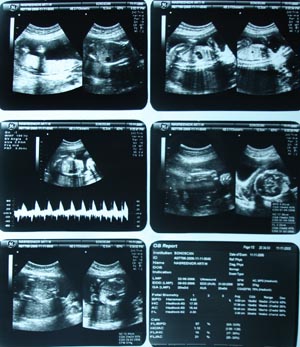

2nd & 3rd trimester USG has its own way of performance. It should include BPD biparital diameter & head circumference (by measuring OFD-occipito Frontal diameter) in addition. Location of placenta with its condition i.e. stages of maturation & position. Foetal abdominal circumference has to be measured at level of adrenal. Vital organs has to be evaluated. Brain & spine has to be given due importance. Amniotic fluid can be assessed by measuring the column of amniotic fluid in all 4 quadrants. Loop of the chord has to be seen. Cosidering all this parameters & confirming about movement of all 4 limbs, & measuring about femur length, gestational period has to be decided. This conclusion has to be matched with LMP (given in h/o) & EDD (expected date of delivery) should be given. Anomaly if present should be discussed with patient or obstetrician & give recommendation.